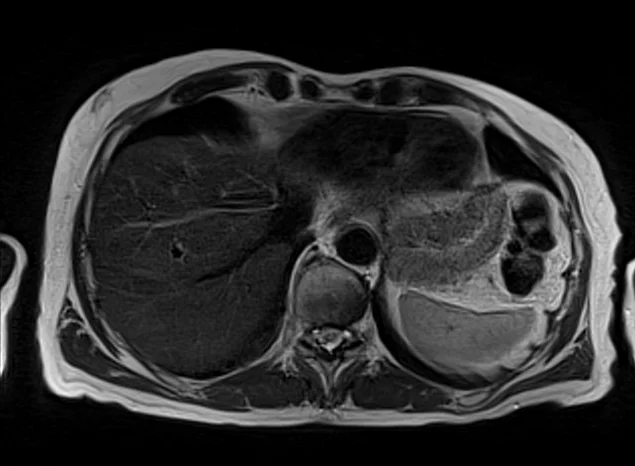

t2 2 - MRI